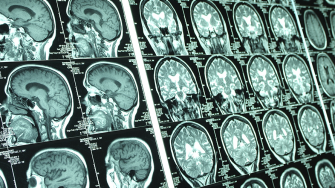

White matter hyperintensities (WMH), sometimes referred to as unidentified bright objects (UBO) - tongue-in-cheek - are abnormally hyperintense (bright) regions in cerebral white matter observed on MRI when particular scans, such as T2-weighted fluid attenuated inversion recovery (FLAIR), are used. They are thought to be the result of reduced blood supply or other kinds of damage to the white matter.  Under the microscope, these regions of WMH show signs of loss of myelin sheath that surrounds the nerve fibres in the white matter, along with some other changes and sometimes total loss of nerve fibres.  Multiple factors, including vascular and genetic components1, can contribute to the development and progression of UBO.

WMHs being to appear in adults in their middle age2,3, and become more severe in older adults and those with diagnosis of stroke, cerebrovascular disease and neurodegenerative diseases. They are an important marker for brain disease in both research and clinical settings. Most commonly, the severity of WMHs in the brain is done by rating a scan on visual inspection.  This is not accurate or precise for research purposes, and is additionally time consuming and requires considerable training and expertise.

Researchers from the Neuroimaging Lab at the Centre for Healthy Brain Ageing (CHeBA) have developed a fully automated pipeline (UBO Detector) to automate the extraction of WMHs.  UBO Detector takes T1-weighted and FLAIR scans as input, provides quality control steps in the middle, and generates both image and text file output to quantify WMHs in various brain regions.

In addition to the global WMH volumes, anatomical locations of WMH also provide crucial information on the likely underlying pathological processes. In UBO Detector, we provide regional WMH measures in lobes and arterial territories, in addition to global WMH volumes. UBO Detector also summarise the number and size of WMHs across the brain.